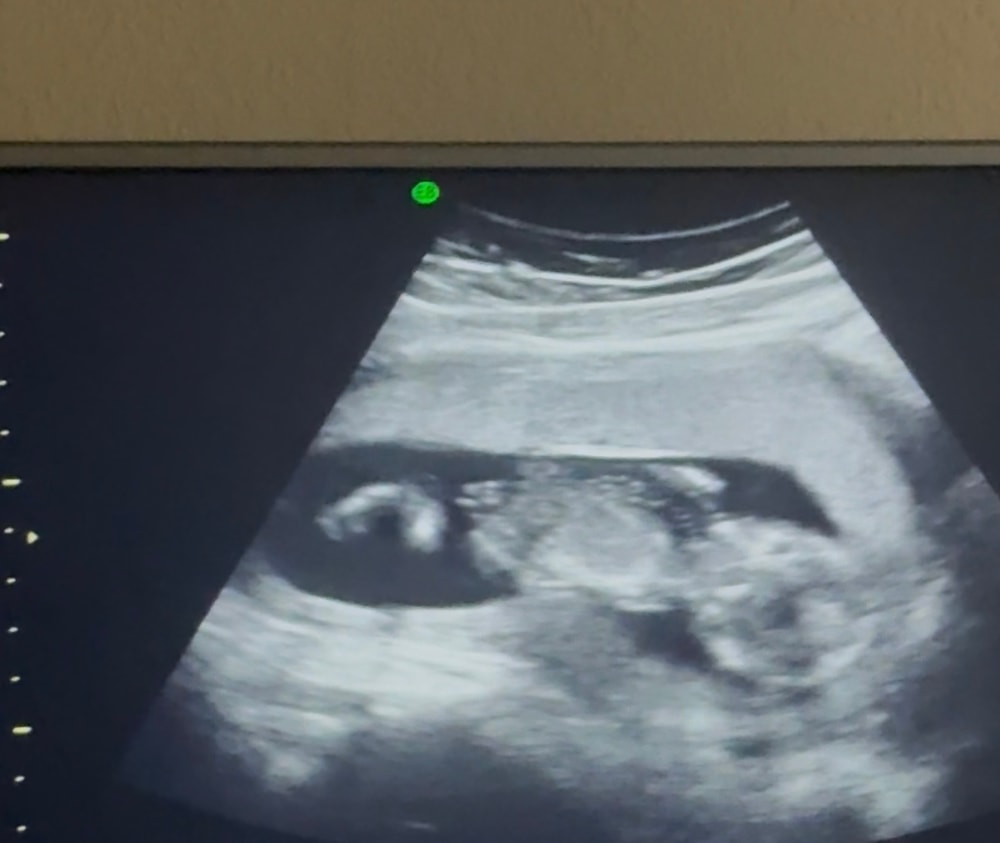

У меня вон его как прижало. И то, врач сказала, что ничего страшного, если нет схваткообразной боли.